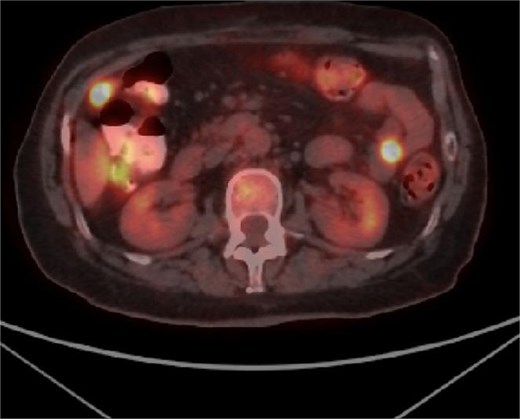

Taking into account clinical and imaging data for obstruction of the small intestine by the tumor and the lack of other options for histological analysis, a decision was made for laparotomy. An ileal tumor measuring ~13 cm/day with necrotic changes, involving the entire small intestine loop with dilatation of the proximal part of the small intestine, and multiple enlarged lymph nodes near the tumor were found (Fig. 3). The tumor also involved the anterior abdominal wall, separately similar lesions were visualized in both ovaries with dimensions of ~5 cm/day. The small intestine was resected with subsequent anastomosis and a total hysterectomy with bilateral salpingo-oophorectomy was performed. The postoperative period was trouble- free and the patient was discharged on the fifth postoperative day, and scheduled for systematic chemotherapy. Positron emission tomography (PET CT) showed the presence of peritoneal lesions, abdominal and pelvic lymph nodes (Fig. 4). Histological analysis established diffuse large B-cell lymphoma (DLBCL), GC subtype involving transmural small intestine, mesenteric lymph nodes, mesovarium, peritoneum. Metastatic nodules adhering to both ovaries. Immunohistochemical study revealed diffuse strong expression of CD 10 and CD 20 in tumor cells, Ki-67- over 90% proliferative activity; MUM1: negative reaction; BCL-6: positive nuclear expression in about 70% of the neoplastic population; CD3,CD5: positive stromal T cells; CD23: membrane expression in small groups of cells at the invasion front; Cyclin D1: lack of expression in tumor cells under positive internal control.

PET CT showing metabolic activity in abdominal and pelvic lymph nodes.